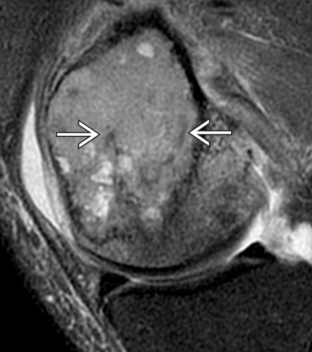

- IRM: zones hypo-T2 (régions fibreuses ou hémorragiques)